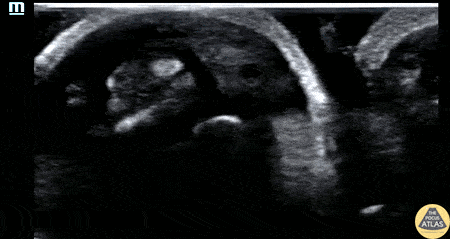

30s M with PMH IVDU presented with worsening swelling over his middle finger and hand. His clinical exam was concerning for flexor tenosynovitis, so a water bath POCUS was performed to evaluate his flexor tendon sheath. The study is shown here, where the middle finger is shown first in short axis and then in long axis. The flexor tendon is seen as the relatively hyperechoic structure just superficial to the bony cortex, and has a fibrillar appearance when seen in long axis. This clip demonstrates anechoic fluid within the sheath surrounding the flexor tendon, which in this clinical context is diagnostic of flexor tenosynovitis, a surgical emergency. This patient was given IV antibiotics and was taken to the operating room for I&D and washout of his hand. Dr. Brigit Noon, PGY3 Denver Health Residency in Emergency Medicine